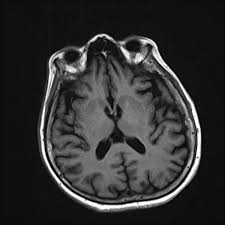

Lewy, the scientist who discovered them. Loss of substantia nigra hyperintensity on 7 tesla mri of parkinson's disease, multiple system atrophy, and progressive supranuclear palsy. Besides nuclear imaging methods, the clinical utility of structural neuroimaging with magnetic resonance imaging (mri) for differential comparison between dementia with lewy bodies and alzheimer's disease. You also might see things that aren't there, called hallucinations. Lbd is a term that covers two conditions that have similar. Protein deposits, called lewy bodies, develop in nerve cells in the brain regions involved in thinking, memory and movement (motor control). Certain nuclear scans of the brain, including positron emission. How is lewy body dementia (ldb) diagnosed? Dr michael firbank discusses his study using functional mri in lewy body dementia and alzheimer's disease at the newcastle university institute. Focal atrophy in dementia with lewy bodies on mri: Memory loss is not always an early symptom. Lewy body dementia (lbd) is a type of progressive dementia. Many people also experience changes in alertness including daytime sleepiness, confusion or staring spells.

The lewy body society (see end of leaflet) is a registered uk charity which has a website full of information. Dementia with lewy bodies or lewy body dementia is dementia caused by the presence of lewy bodies in the brain. Loss of substantia nigra hyperintensity on 7 tesla mri of parkinson's disease, multiple system atrophy, and progressive supranuclear palsy. Also, there is a helpline for support provided by dementia. It is reported as the second most common form of dementia following alzheimer diseas.